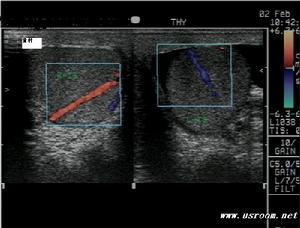

B超檢查可進一步明確診斷,對疑為睪丸腫瘤引起的繼發性睪丸鞘膜積液有重要意義、

B超檢查可進一步明確診斷,特別對疑為睪丸腫瘤引起的繼發性睪丸鞘膜積液有重要意義。